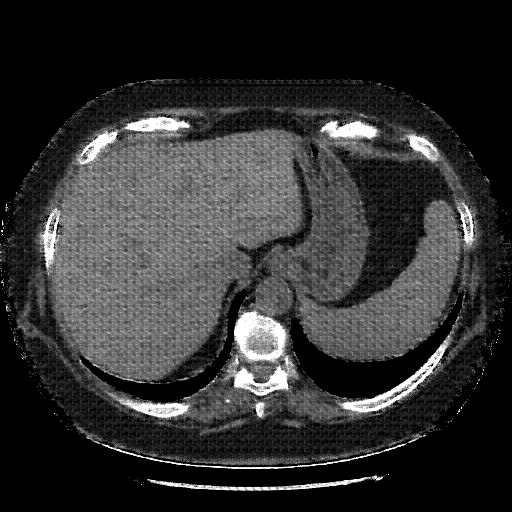

Generated VENOUS CT scan (A→B translation)

Full window (WL 1023.5, WW 4095 β†’ Low βˆ’1024, High +3071)

Lung window (WL -600, WW 1500 β†’ Low βˆ’1350, High +150)

Mediastinum window (WL 40, WW 400 β†’ Low βˆ’160, High +240)